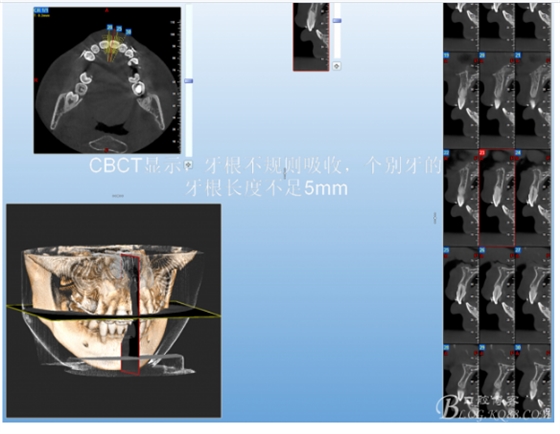

有15%的人在正畸治療前就已經(jīng)發(fā)生牙根吸收,這與激素失衡和飲食缺乏有關(guān)。正畸治療后12個(gè)月,牙根再吸收的發(fā)生率增加到73%,有25%的正畸治療患者根尖吸收超過(guò)2mm,約5%的人發(fā)生超過(guò)5mm的嚴(yán)重吸收。

大多數(shù)研究認(rèn)同牙根再吸收的嚴(yán)重性與正畸治療的持續(xù)時(shí)間、力量大小相關(guān)。臨床醫(yī)師應(yīng)該采用輕力、高效的矯治手段進(jìn)行正畸治療,并在正畸治療前、中、后進(jìn)行X線檢查對(duì)比,觀察牙根再吸收的發(fā)生情況。研究發(fā)現(xiàn):間斷治療的患者其牙根再吸收量明顯少于那些持續(xù)治療的患者。應(yīng)用力的中斷有助于已破壞的牙周組織重建并減少牙根的進(jìn)一步縮短。